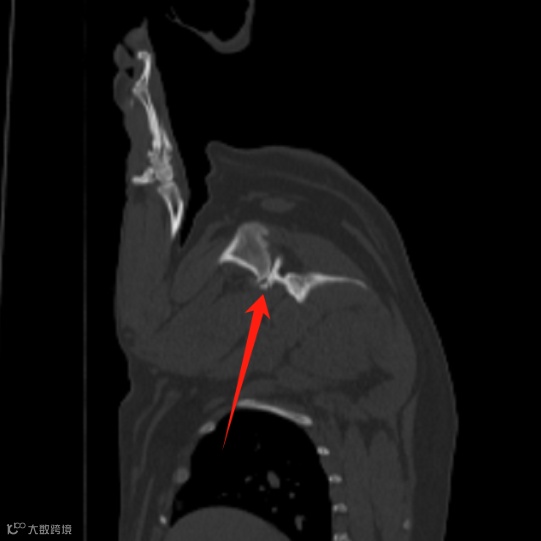

偶尔性右前肢跛行,右肩关节小游离体。